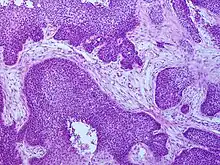

One method of classifying squamous-cell carcinomas is by their appearance under microscope. Subtypes may include:

- basaloid squamous-cell carcinoma is mostly found in or near the tongue, tonsils, or larynx, but may also occur in the lung or elsewhere.[24]

Basaloid squamous-cell carcinoma